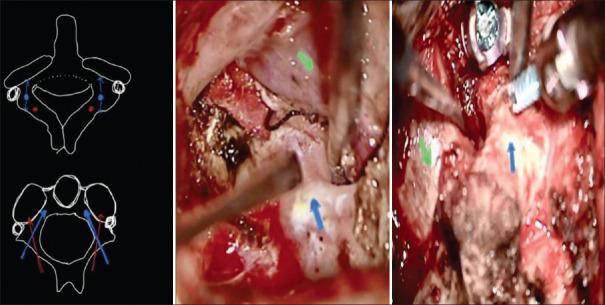

From January 2017 to December 2022, 682 consecutive C1 C2 screws in 215 patients with craniovertebral junction (CVJ) anomalies were enrolled. All patients underwent posterior fixation with K and D technique without any fluoroscopic guidance. The patient's demographic details, clinical details, radiological details, major intraoperative events, and postoperative complications were noted. The screws malposition grades and direction on CT images in the axial and sagittal plane were defined as new per proposed "SGPGI accuracy criteria." All patients had a clinical evaluation at 3-month follow-up.

Total 682 C1, C2 screws were placed in 215 patients for CVJ anomalies using K and D technique. The accuracy of screws placement by freehand technique was 84.46% (576/682). So with technique explained the rate of malplacement in simple (16.35%) and complex (15.19%) groups were almost comparable and comparison difference was not significant ( = 0.7005).

The freehand technique, as described, is effective in cases of anomalous bony anatomy, and it is mandatory in complex CVJ anomalies. The accuracy of screw placement and VA injury is comparable with major studies. This technique is supposedly cost-effective and less hazardous to both health-care workers and patients.